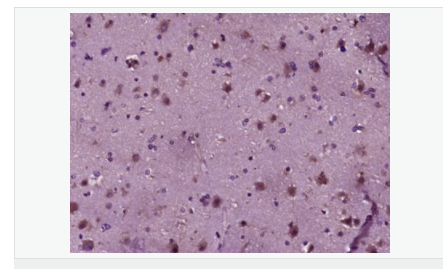

產(chǎn)品應(yīng)用ELISA=1:5000-10000 IHC-P=1:100-500 (石蠟切片需做抗原修復(fù))

免 疫 原KLH conjugated synthetic peptide derived from human cAMP Protein Kinase Catalytic subunit:1-100/351

產(chǎn)品介紹This gene encodes one of the catalytic subunits of protein kinase A, which exists as a tetrameric holoenzyme with two regulatory subunits and two catalytic subunits, in its inactive form. cAMP causes the dissociation of the inactive holoenzyme into a dimer of regulatory subunits bound to four cAMP and two free monomeric catalytic subunits. Four different regulatory subunits and three catalytic subunits have been identified in humans. cAMP-dependent phosphorylation of proteins by protein kinase A is important to many cellular processes, including differentiation, proliferation, and apoptosis. Constitutive activation of this gene caused either by somatic mutations, or genomic duplications of regions that include this gene, have been associated with hyperplasias and adenomas of the adrenal cortex and are linked to corticotropin-independent Cushing's syndrome. Alternative splicing results in multiple transcript variants encoding different isoforms. Tissue-specific isoforms that differ at the N-terminus have been described, and these isoforms may differ in the post-translational modifications that occur at the N-terminus of some isoforms. [provided by RefSeq, Jan 2015]